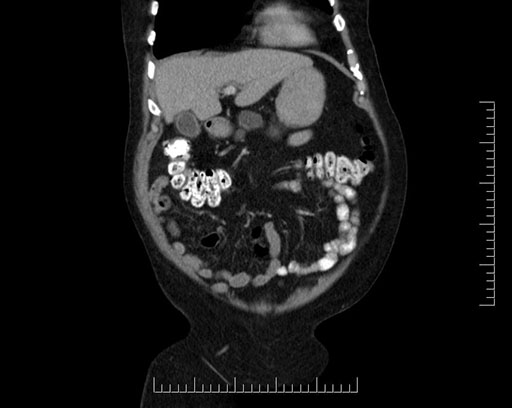

Imaging Analysis

Look through the patient's CT scan to identify any areas of concern for the necessary procedure.

Based on your CT findings, which issue(s) would give reason for "planned slowing down moment(s)" in this case?

Considering a standard Whipple procedure, what step(s) of the operation would you do differently in this case?